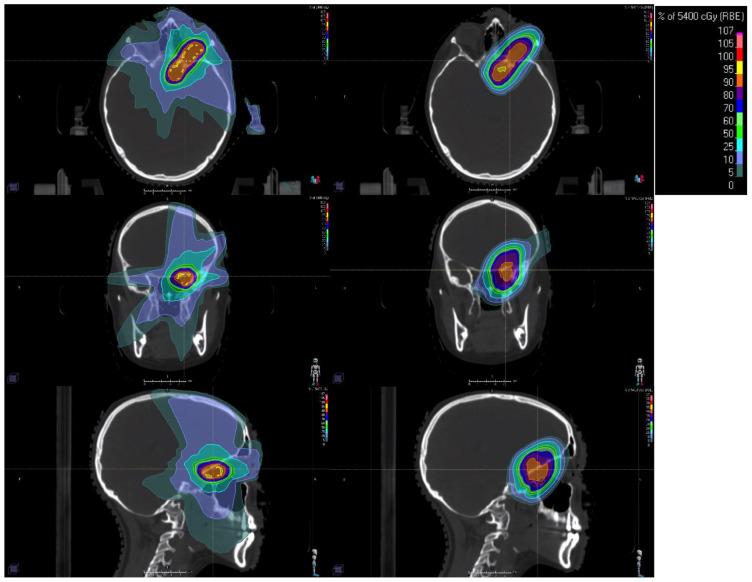

Radiation therapy (RT) is a cornerstone in the management of pediatric central nervous system (CNS) tumors. Recent advancements in RT delivery and techniques aim to enhance therapeutic effectiveness while minimizing both acute and long-term complications associated with pediatric brain RT. This paper highlights innovative developments in the field, including the clinical indications, benefits, and challenges of proton therapy and stereotactic radiotherapy. The ongoing refinement of risk-adapted RT volumes is highlighted, with examples of newly proposed germinoma RT volumes and hippocampal-sparing RT. Additionally, emerging experimental approaches, including FLASH therapy and theranostics, are also discussed as promising future directions. Further prospective, multi-institutional collaborative studies are essential to validate and expand upon the benefits outlined in this review.

放射治疗(RT)是小儿中枢神经系统(CNS)肿瘤管理的基石。放射治疗的交付和技术方面的最新进展旨在提高治疗效果,同时将与小儿脑部放疗相关的急性和长期并发症降至最低。本文重点介绍了该领域的创新发展,包括质子治疗和立体定向放射治疗的临床适应症、益处和挑战。文中强调了风险适应性放疗体积的不断完善,并列举了新提出的生殖细胞瘤放疗体积和海马体保留放疗的例子。此外,还讨论了包括FLASH治疗和治疗诊断学在内的新兴实验方法,认为它们是有前景的未来发展方向。进一步的前瞻性、多机构合作研究对于验证和扩展本综述中概述的益处至关重要。